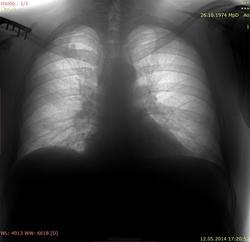

Досняли. Первый снимок был с неполным вдохом. Уже собиралась отправлять в ПТД.

Надеюсь, полегчало?

Т.е. по первому снимку сразу можно было сказать, что это сосуды?

Конечно.

[/quote] Здесь нет одностороннего поражения. А на полноту вдоха-выдоха ( смотрите- на каком уровне купол диафрагмы) всегда обращайте внимание и небольшой разворот, особенно у детей- сразу " вылечите" от многих болезней![/quote] ++

Вот видите, как легко и просто. А КТ-шники даже на нативе, зачастую, не могут ответить на этот вопрос. Только законтрастировав.

Ну, и на структуру самих корней внимание обращайте. Старайтесь различить сосуды, спокойно, не торопясь... Книгу Вам уже посоветовали. И нормы побольше в память откладывайте. Без этого и Никто никак.:)